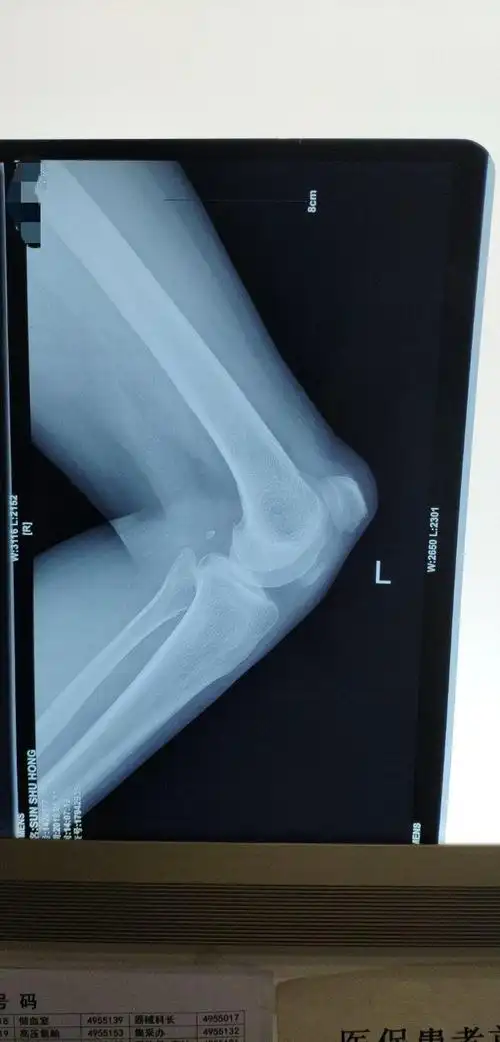

髌骨骨折